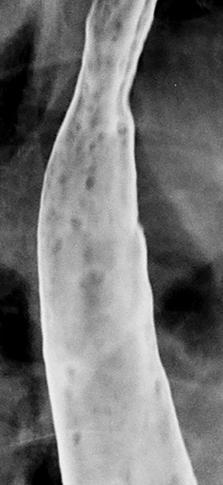

Image en lacule intra

oesophagien : TOGD de oesophage |

Lipome oesophagien : IRM en coupe

axiale |